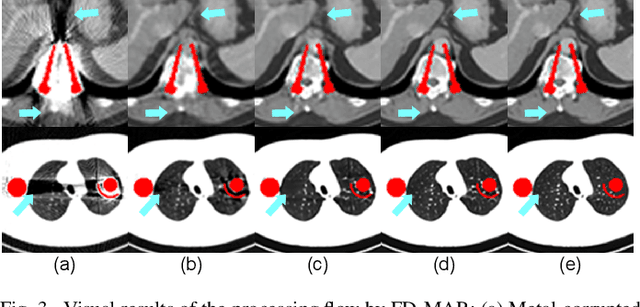

Abstract:The presence of high-density objects such as metal implants and dental fillings can introduce severely streak-like artifacts in computed tomography (CT) images, greatly limiting subsequent diagnosis. Although various deep neural networks-based methods have been proposed for metal artifact reduction (MAR), they usually suffer from poor performance due to limited exploitation of global context in the sinogram domain, secondary artifacts introduced in the image domain, and the requirement of precise metal masks. To address these issues, this paper explores fast Fourier convolution for MAR in both sinogram and image domains, and proposes a Fourier dual-domain network for MAR, termed FD-MAR. Specifically, we first propose a Fourier sinogram restoration network, which can leverage sinogram-wide receptive context to fill in the metal-corrupted region from uncorrupted region and, hence, is robust to the metal trace. Second, we propose a Fourier refinement network in the image domain, which can refine the reconstructed images in a local-to-global manner by exploring image-wide context information. As a result, the proposed FD-MAR can explore the sinogram- and image-wide receptive fields for MAR. By optimizing FD-MAR with a composite loss function, extensive experimental results demonstrate the superiority of the proposed FD-MAR over the state-of-the-art MAR methods in terms of quantitative metrics and visual comparison. Notably, FD-MAR does not require precise metal masks, which is of great importance in clinical routine.